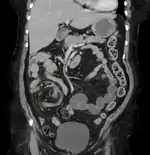

Volvulus with gangrene of the sigmoid